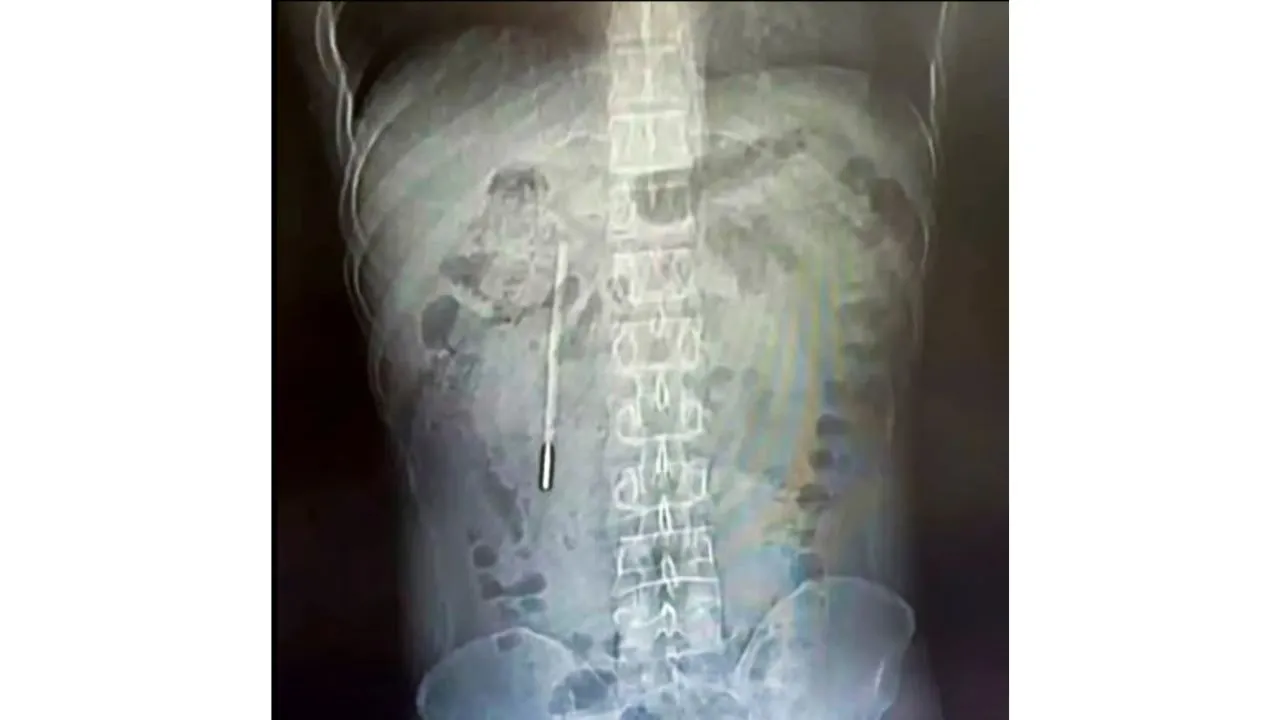

Durante los exámenes, una tomografía reveló la presencia de un objeto extraño alojado en el duodeno, la primera parte del intestino delgado.

Tras el análisis, los especialistas concluyeron que se trataba de un termómetro de mercurio.

La ubicación del objeto generó preocupación inmediata, ya que la punta del termómetro estaba en contacto con la pared intestinal, lo que representaba un alto riesgo de perforación y hemorragia interna si no se intervenía a tiempo.